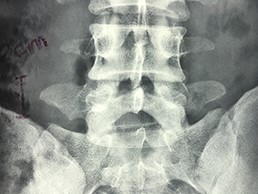

A 42-year-old female presented to the clinic with a history of chronic low back pain. She reported no relevant medical history. She had already been treated in the last 4 years by general practitioners with analgesics and home based physiotherapy with no satisfactory results. She had two previous admissions to the emergency department where morphine was prescribed to control the pain on her lower back. She was under ambulatory treatment with diclofenac, and tizanidine with partial relief of symptoms. Her main complaint was pain on the lower lumbar back with no radiation to the lower extremities. In her physical evaluation she presented limitation to full rotation and bending of the lumbar spine due to pain. Lasegue sign was negative, sensitivity, reflexes, sagittal balance, distal muscular strength and pulses were normal. Radiographs showed an overdeveloped left transverse process of the fifth lumbar vertebra which contacts with the sacrum at the left sacral wing with signs of degeneration at the same site (Fig. 1). Magnetic resonance imaging (MRI) studies were obtained (Figs 2–5). The patient was taken to the operating room where infiltration with 1 mL of lidocaine and 40 mg of Triamcinolone was performed in the pseudoarticulation between the left transverse process and the sacrum under fluoroscopic guidance. She reported a complete relief of pain after the procedure. At three months follow-up she was managed with strengthening and stabilizing exercises for the lumbar spine and postural education was initiated. She remains asymptomatic at her 12 months follow up.

Radiographs showing an overdeveloped left transverse process, which contacts with the sacrum left sacral wing (Castelvi’s Type IIa).

Showing the protective effect of the limitation of the motion in the distal disc to the anomaly.

The partial fusion at the lower part of the lumbosacral transition produces important alterations in normal biomechanics at the levels immediately above and below the LSTV. Changes such as hypermobility and abnormal torque moments are present at the level above the LSTV, predisposing it to early degeneration (early disc pathology and facet joint degenerative disease). Restricted movement below the LSTV produces a protective effect against degeneration of disc and facets and is related to changes (facets are smaller and coronally oriented) in the dimensions of the lower level facet joints [7]. These alterations can be verified in the adjacent levels of the LSTV in our patient.